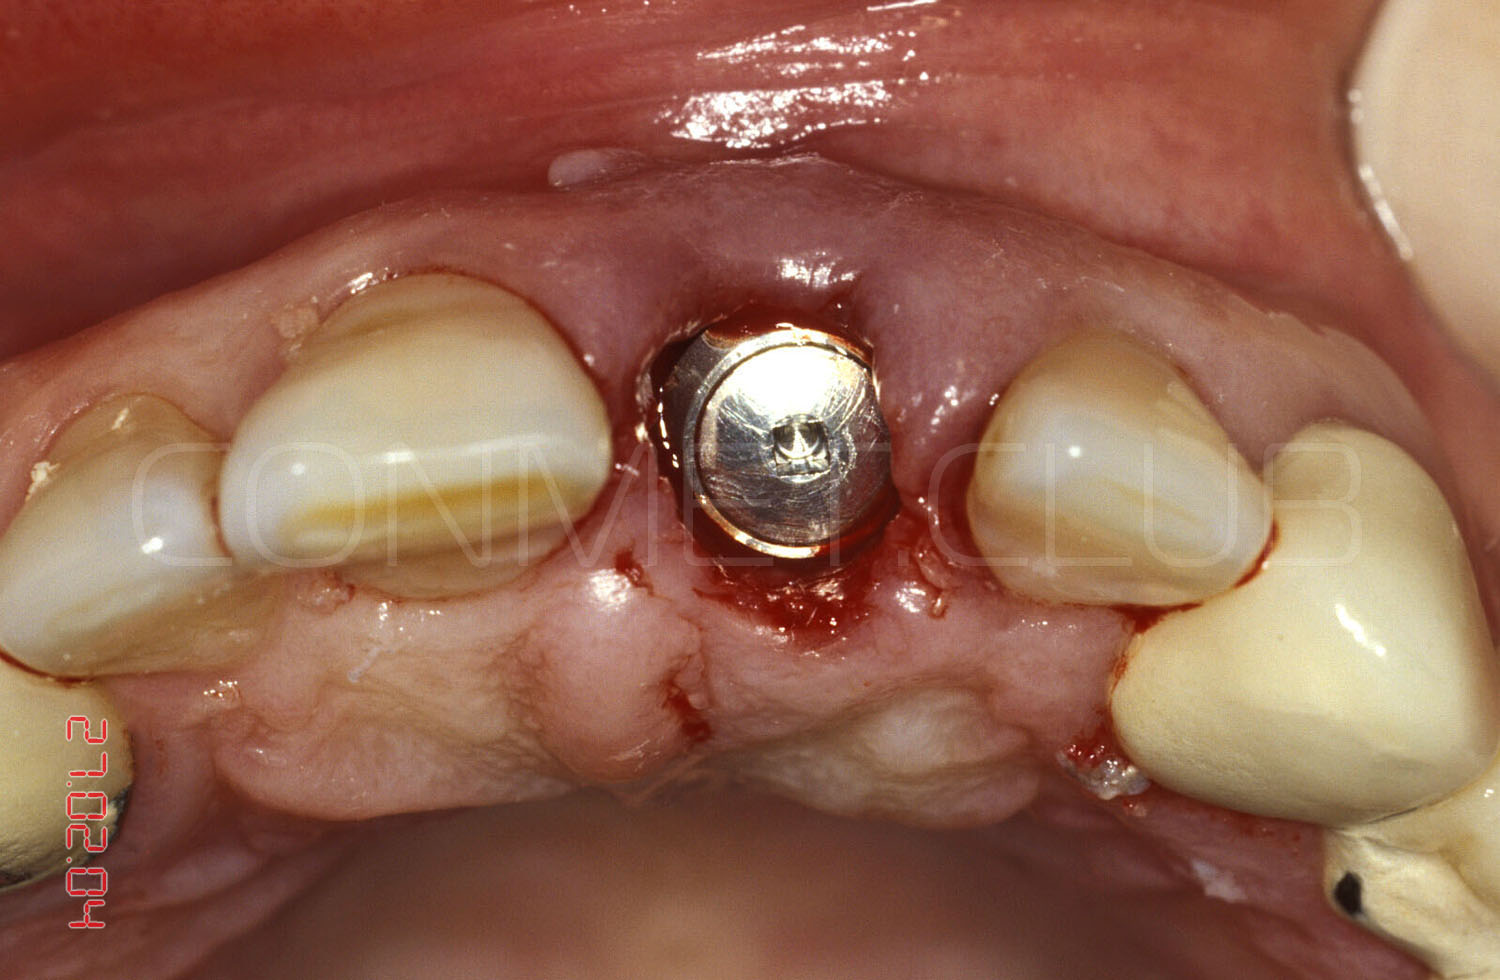

Сразу после экстракции зуба 21 производится установка имплантата КОНМЕТ с полированной трансгингивальной частью высотой более 3 мм. Интерфейс имплантата - просто конус Морзе и ни каких антиротационных шестигранников!

Имплантат установлен и зафиксирован винт-заглушка. Обратите внимание, что даже при столь широком экваторе имплантата не удалось полностью перекрыть диаметр костной альвеолы в направление зуба 11. Швы не накладывались и поверхность имплантата закрывалась мазью Солкосерил Дентал

В этот же день была изготовлена провизорная коронка крепившаяся к соседним зубам на стекловолоконную ленту и композитный цемент.